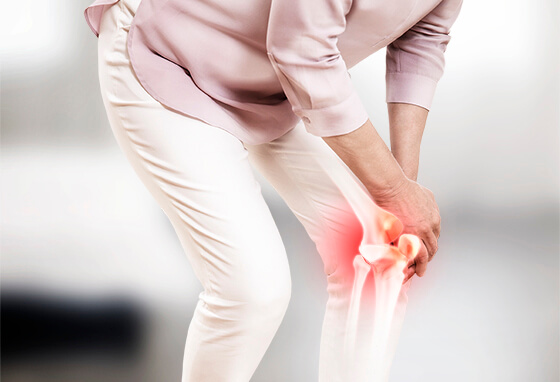

10. 류마티스 관절염 초기증상 : 관절 통증

류마티스 관절염 초기증상에서 흔한 증상으로써 관절을 싸고 있는 활액막에 염증이 발생하며 진행될수록 점차 주변 연골과 뼈로 염증이 퍼지게 되는데 그 결과 온몸의 모든 관절이 쑤시고 저리면서 뻣뻣해지는 것을 시작으로서 관절의 통증, 후끈거림, 압통과 같이 붓기가 발생해요. 보통 양쪽 관절에 이러한 증상들이 발생하게면서 손목, 팔꿈치, 무릎, 손가락, 발가락 부터 관절에 많은 양 발생한다고 해요.